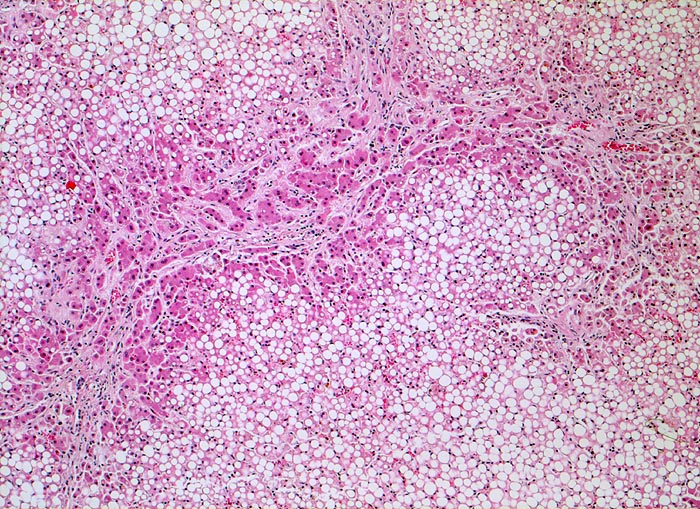

PathoPic – image database / PathoPic ID 4767 - unvollständiger zirrhotischer Umbau, Steatose

unvollständiger zirrhotischer Umbau, Steatose

Bindgewebebige Septen durchziehen das grobtropfig verfettete Parenchym und bilden einen unvollständigen Knoten.

Für die Diagnose einer Leberzirrhose wird ein diffuser knotiger Umbau der gesamten Leber gefordert. Die Grenzen zwischen unvollständigem und vollständigem zirrhotischem Umbau sind fliessend.